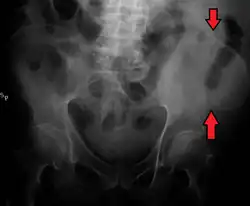

La cresta ilíaca es el nombre que recibe el borde superior del ala del ilion que se extiende hasta el margen de la pelvis mayor. La cresta ilíaca es palpable tanto en un hombre como en una mujer en toda su extensión,[1] de forma general convexa y levemente curva o sinuosa con concavidad interna en el frente y hacia afuera por detrás. Deja en su interior una cavidad que a menudo se denomina fosa iliaca.

La cresta ilíaca es más angosta hacia el centro que en los extremos y termina en la espina ilíaca antero-superior y posterior. La superficie de la cresta ilíaca es amplia y se puede dividir en un labio lateral o externo y un labio medial o interno y entre estos, una línea intermedia.[1]

A unos 5 cm detrás de la espina ilíaca anterosuperior se encuentra una prominencia sobre el labio externo, conocido como el tubérculo ilíaco (tuberculum iliacum). Hacia el labio externo se insertan los músculos tensor de la fascia lata,[2] oblicuo mayor del abdomen y el músculo dorsal ancho. La fascia lata, que es la aponeurosis profunda del muslo, corre la extensión de la cresta ilíaca hasta llegar al músculo oblicuo menor del abdomen.

Sobre el labio interno de la cresta ilíaca se insertan los músculos transverso del abdomen, cuadrado lumbar, sacroespinal y el psoasilíaco.[2]